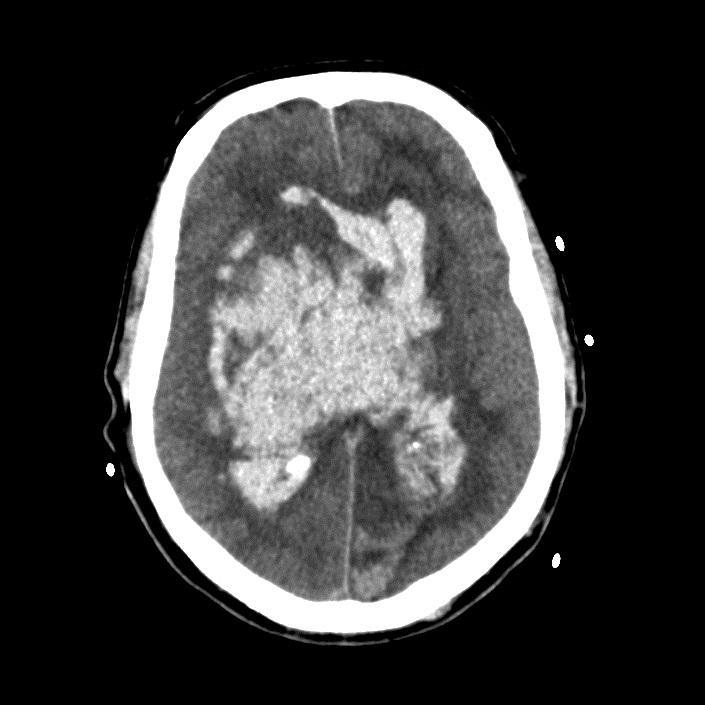

Massive ICH